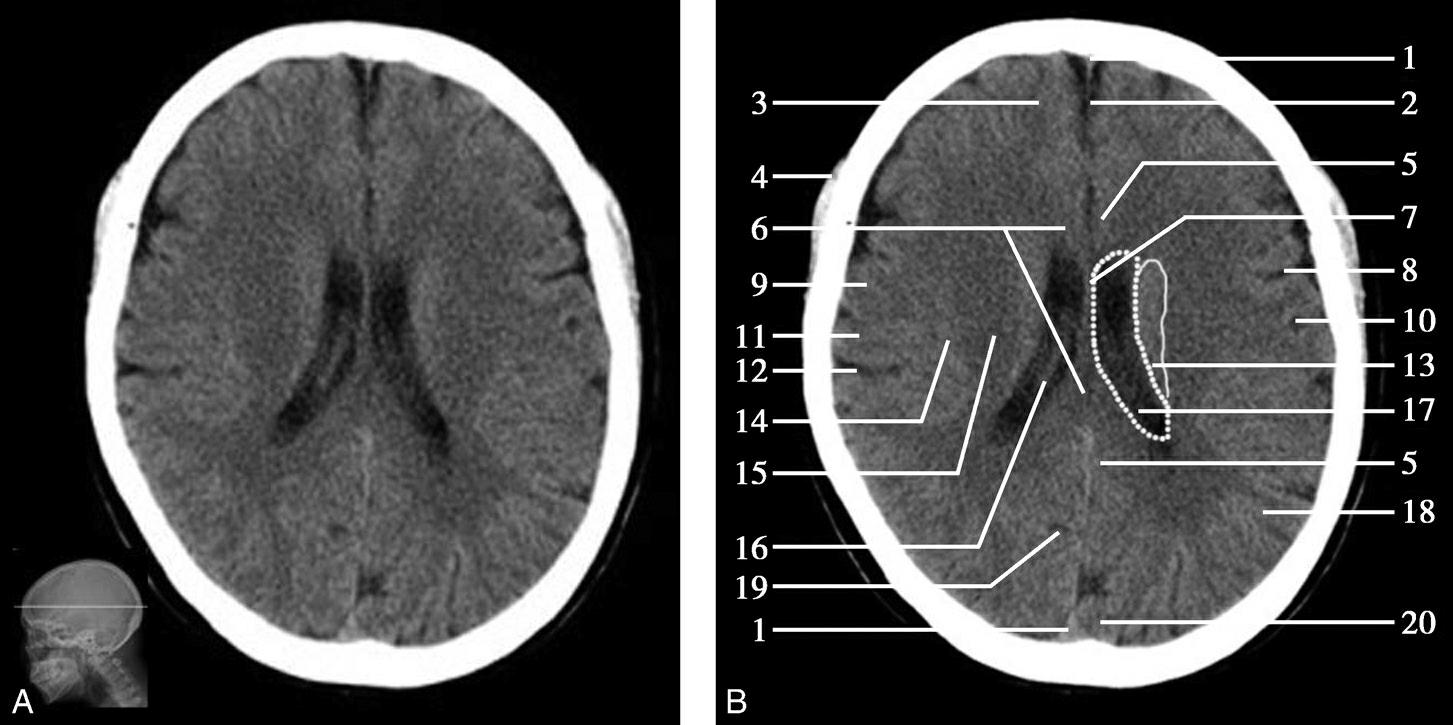

Alberta卒中项目早期CT评分(Alberta stroke program early CT score,ASPECTS)是一种评价急性缺血性卒中患者大脑中动脉供血区早期缺血性改变的简单、可靠、系统化的方法,是常用的脑卒中评定量表之一,可对缺血性病变快速进行半定量评价,有助于判定溶栓效果和远期预后。该评分主要基于CT平扫,具体分区如下(图1-2-76)所示,即选取大脑中动脉供血区2个层面。分区后共10个区域,每个区域记1分。评分时任何区域只要有低密度灶,则扣除该区域得分。正常脑ASPECTS评分为满分(10分),若MCA供血区广泛梗死累及全部区域时,则ASPECTS评分为0分。

图1-2-76 ASPECTS评分脑组织分区

A.在基底节层面(即丘脑和纹状体平面),分为各级分支M 1 、M 2 、M 3 、岛叶(缩写I)、豆状核(缩写L)、尾状核(缩写C)和内囊(缩写IC)后肢等7个区域;B.在基底节以上层面(基底节层面上2cm),包括M 4 、M 5 和M 6 。